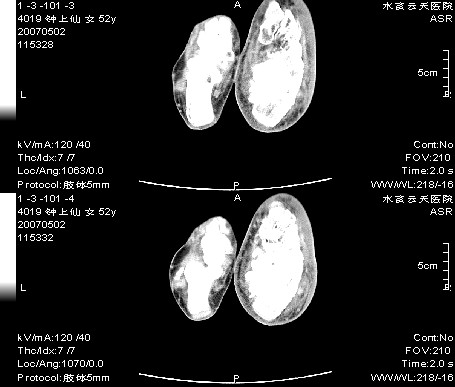

右足跗骨关节面毛糙,滑膜下多发虫蚀状破坏区,周围有硬化边,软组织肿胀明显,首先考虑关节结核;结合实验室检查及平片排除创伤性关节炎合并化脓性感染。

右足跗骨关节面毛糙,滑膜下多发虫蚀状破坏区,并形成空洞及见空洞内死骨,周围有硬化边,软组织肿胀明显,支持首先考虑:右足跗骨结核。

右跟骨轻度膨胀,轮廓不规则,见明显增生硬化,且见斑片状骨破坏及小死骨形成,有软组织肿胀明显,皮下脂肪密度增高。考虑右跟骨陈旧性骨折,右跟骨化脓性骨髓炎

右足跗骨关节面毛糙,滑膜下多发虫蚀状破坏区,并形成空洞及见空洞内死骨,周围有硬化边,软组织肿胀明显,支持首先考虑:1:右糖尿病足,查血糖.2右足骨髓炎

右足跗骨关节面毛糙,滑膜下多发虫蚀状破坏区,周围有硬化边,软组织肿胀明显,首先考虑创伤性关节炎合并化脓性感染;结关节结核合实验室检查及平片排除。